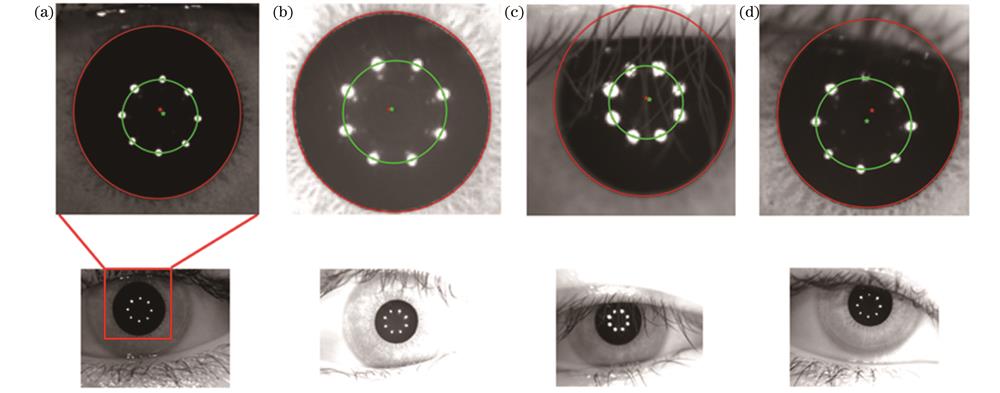

The FMTG algorithm proposed in this paper has a sharper evaluation curve shape and a stronger ability to distinguish on-focus images from out-of-focus images (Fig. 10). Its average calculation time is about 13 ms, with a sharpness ratio of 93.531, and the sensitivity is 0.329, which are all better than that of other six traditional evaluation algorithms and reflect good unimodality and accuracy (Table 1). The error curve of the LPC algorithm proposed in this paper has small fluctuation and good stability, and the algorithm can adapt to certain environmental changes (Fig. 12). The average calculation time of the LPC algorithm is 10.2 ms, with an accuracy of 97.14%, and the average error is 1.4 pixel, which indicate that the LPC algorithm has been greatly improved compared with the Hough method and the improved Hough method (Table 2). In addition, the proposed LPC algorithm can adapt to lighting environments with different brightness and darkness and situations where the pupil is partially occluded, and thus it shows good universality (Fig. 13).

This paper proposed a human eye autofocus and pupil center auto-alignment system applied to ophthalmic measuring instruments. The system realized the autofocus of the human eye region through an autofocus algorithm based on the FMTG algorithm and then delimited the ROI window through a convolutional neural network. In addition, it adopted an ellipse recognition and fitting algorithm to accurately locate the pupil center and optical axis and finally used the mechanical movement of the three-axis high-precision displacement stage to achieve the alignment of the human eye pupil center and optical axis. The experimental results show that the average calculation time of the FMTG algorithm proposed in this paper is about 13 ms, and the evaluation indicators such as sharpness ratio and sensitivity are higher than those of the traditional algorithms, and the FMTG algorithm has good unimodality and accuracy. The proposed LPC algorithm has an average calculation time of 10.2 ms and an accuracy of 97.14%. It can adapt to complex environments with different lighting and partially occluded pupils and has great accuracy and universality. The experimental results show that the system built in this paper can meet the requirements of accuracy, timeliness, and robustness of ocular biological parameter measurement, improve the automation level of the instruments, and contribute to the intelligent development of ophthalmic measurement instruments.

本文算法还在不同光线和瞳孔部分遮挡等复杂条件下进行了测试。

图 13. 复杂条件下本文算法的处理结果。(a)暗光条件;(b)亮光条件;(c)(d)瞳孔部分遮挡

Fig. 13. Processing results of algorithm in this paper under complex conditions. (a) Dark light condition; (b) bright light condition; (c)(d) partial occlusion of pupil